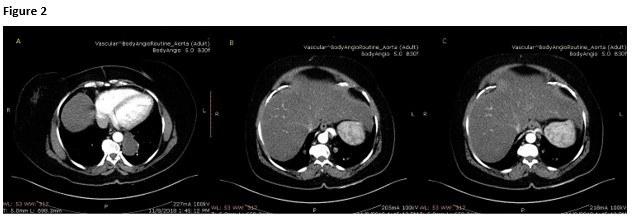

Routine labs were within normal limits. Her chest film and chest CT scan with IV contrast are shown below (Figure 1).